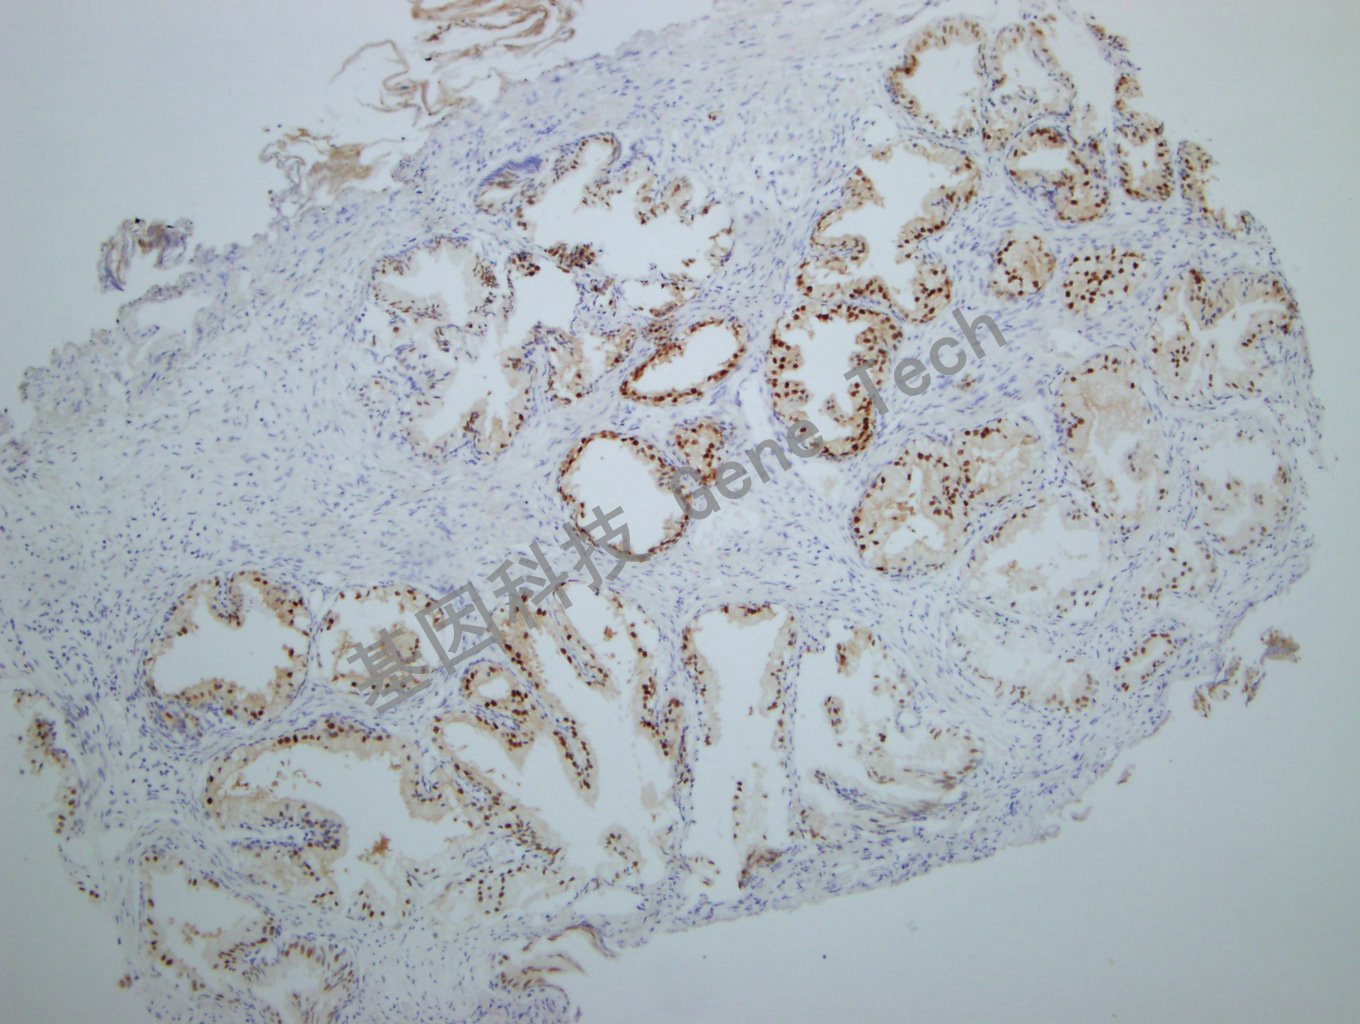

前列腺石蜡切片,用 NKX3.1(GT2260)染色,细胞核阳性,DAB 显色。(10×)